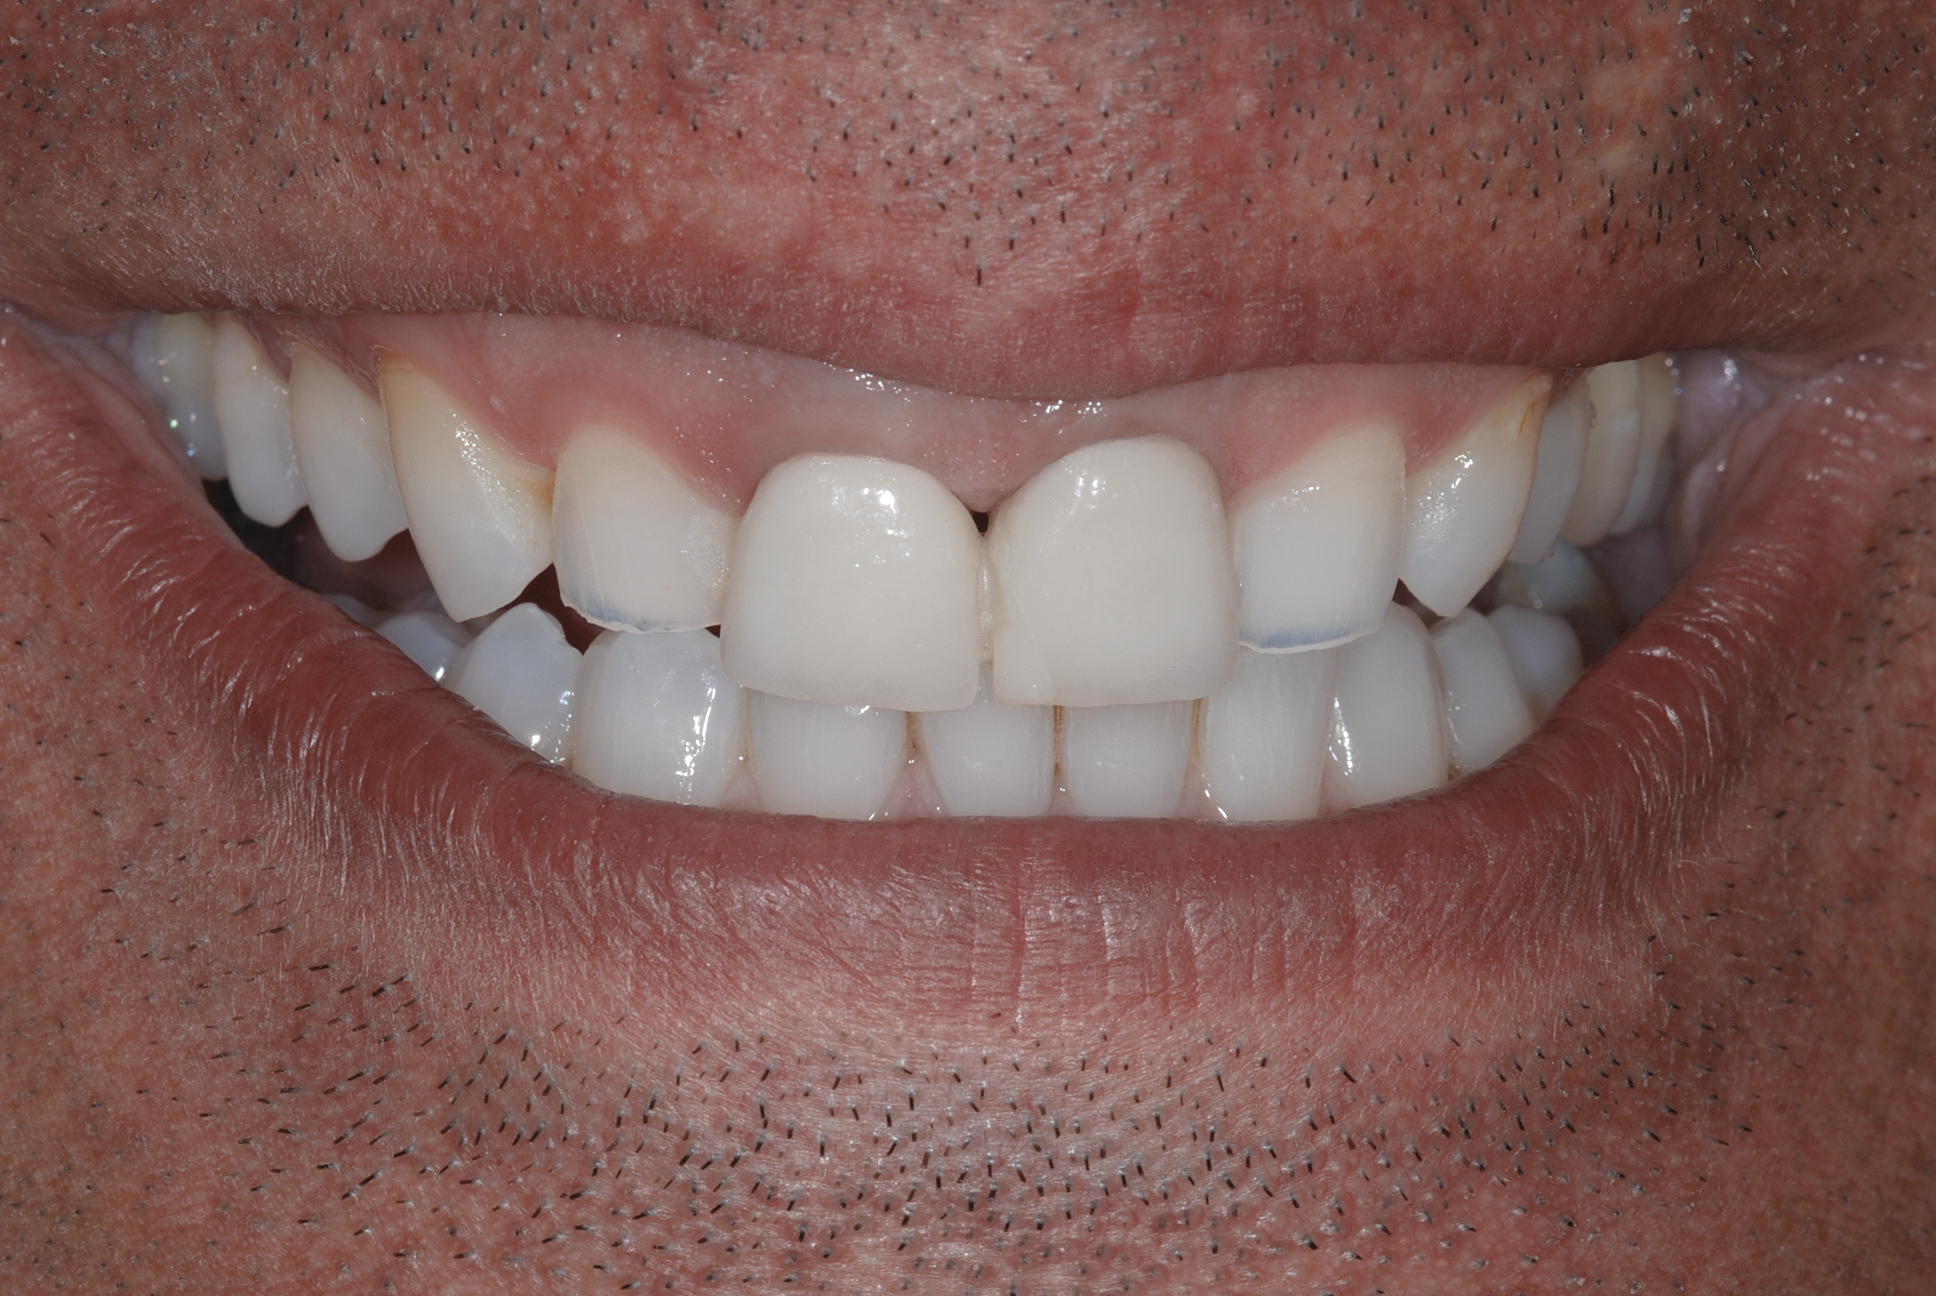

Fig 2. Resolution of gummy smile after treatment in patient shown in Fig 1.

Figure 2